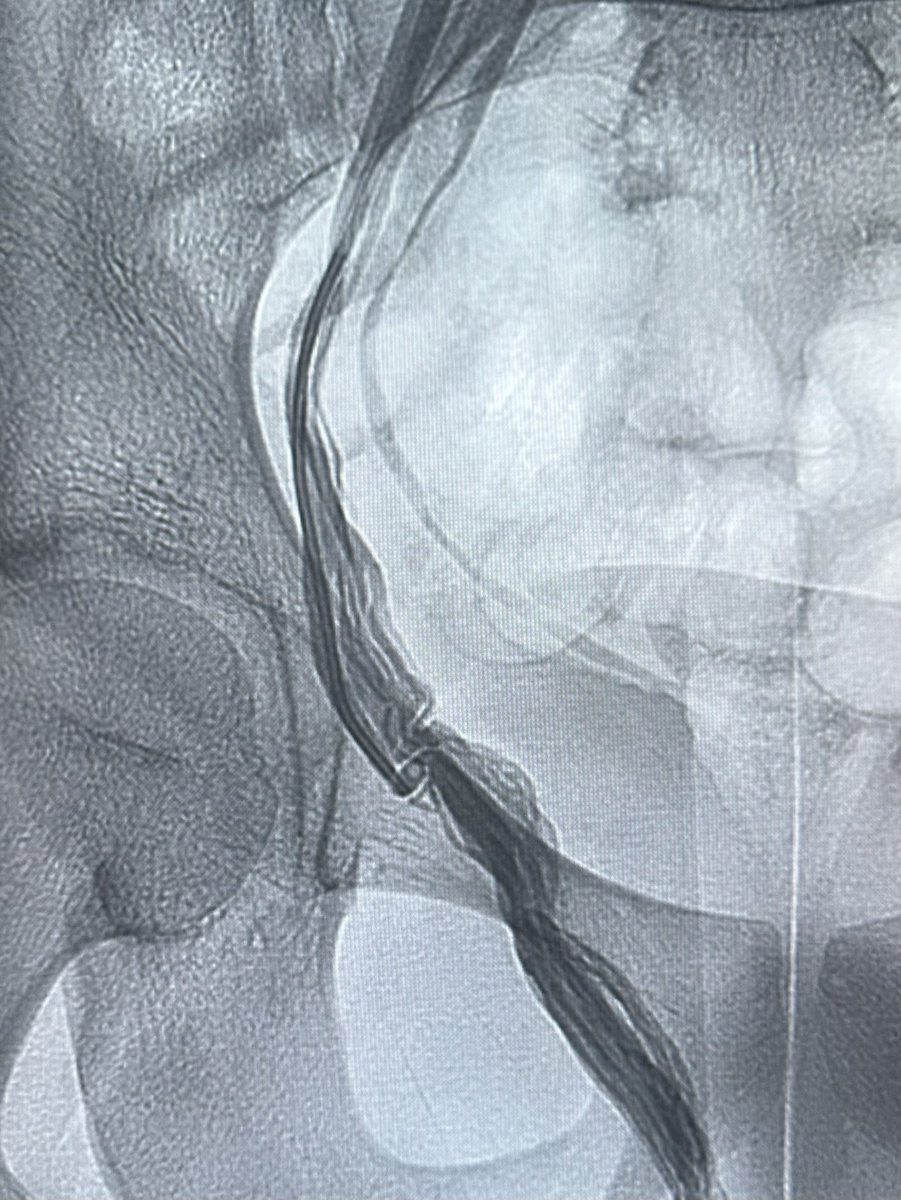

علاج دوالي الخصية بالأشعة التداخلية ، العلاج بالصمغ الطبي يعتبر أفضل وأحدث علاج. يتم إغلاق الدوالي والأوردة بدقة دون التعرض للشرايين والقنوات الليمفاوية الدقيقة. مثال لمريض لديه ما يفوق عن ٤٠ وريد ، لا يمكن ربطها جميعاً جراحياً. بالقسطرة؟ انتهينا من الجهتين خلال اقل من ١٠ دقائق.

طريقة تغلغل الصمغ الطبي في علاج الأوردة المغذية لدوالي الخصية بالقسطرة. اغلاق جميع الأوردة بدون المساس بالقنوات الليمفاوية (فلا يحصل قيلة مائية) ولا الشعيرات الشريانية الدقيقة (فلا يحصل ضمور) القسطرة والأشعة التداخلية اثبتت بالابحاث افضليتها على الجراحة من كل النواحي

علاج دوالي الخصيتين بالقسطرة